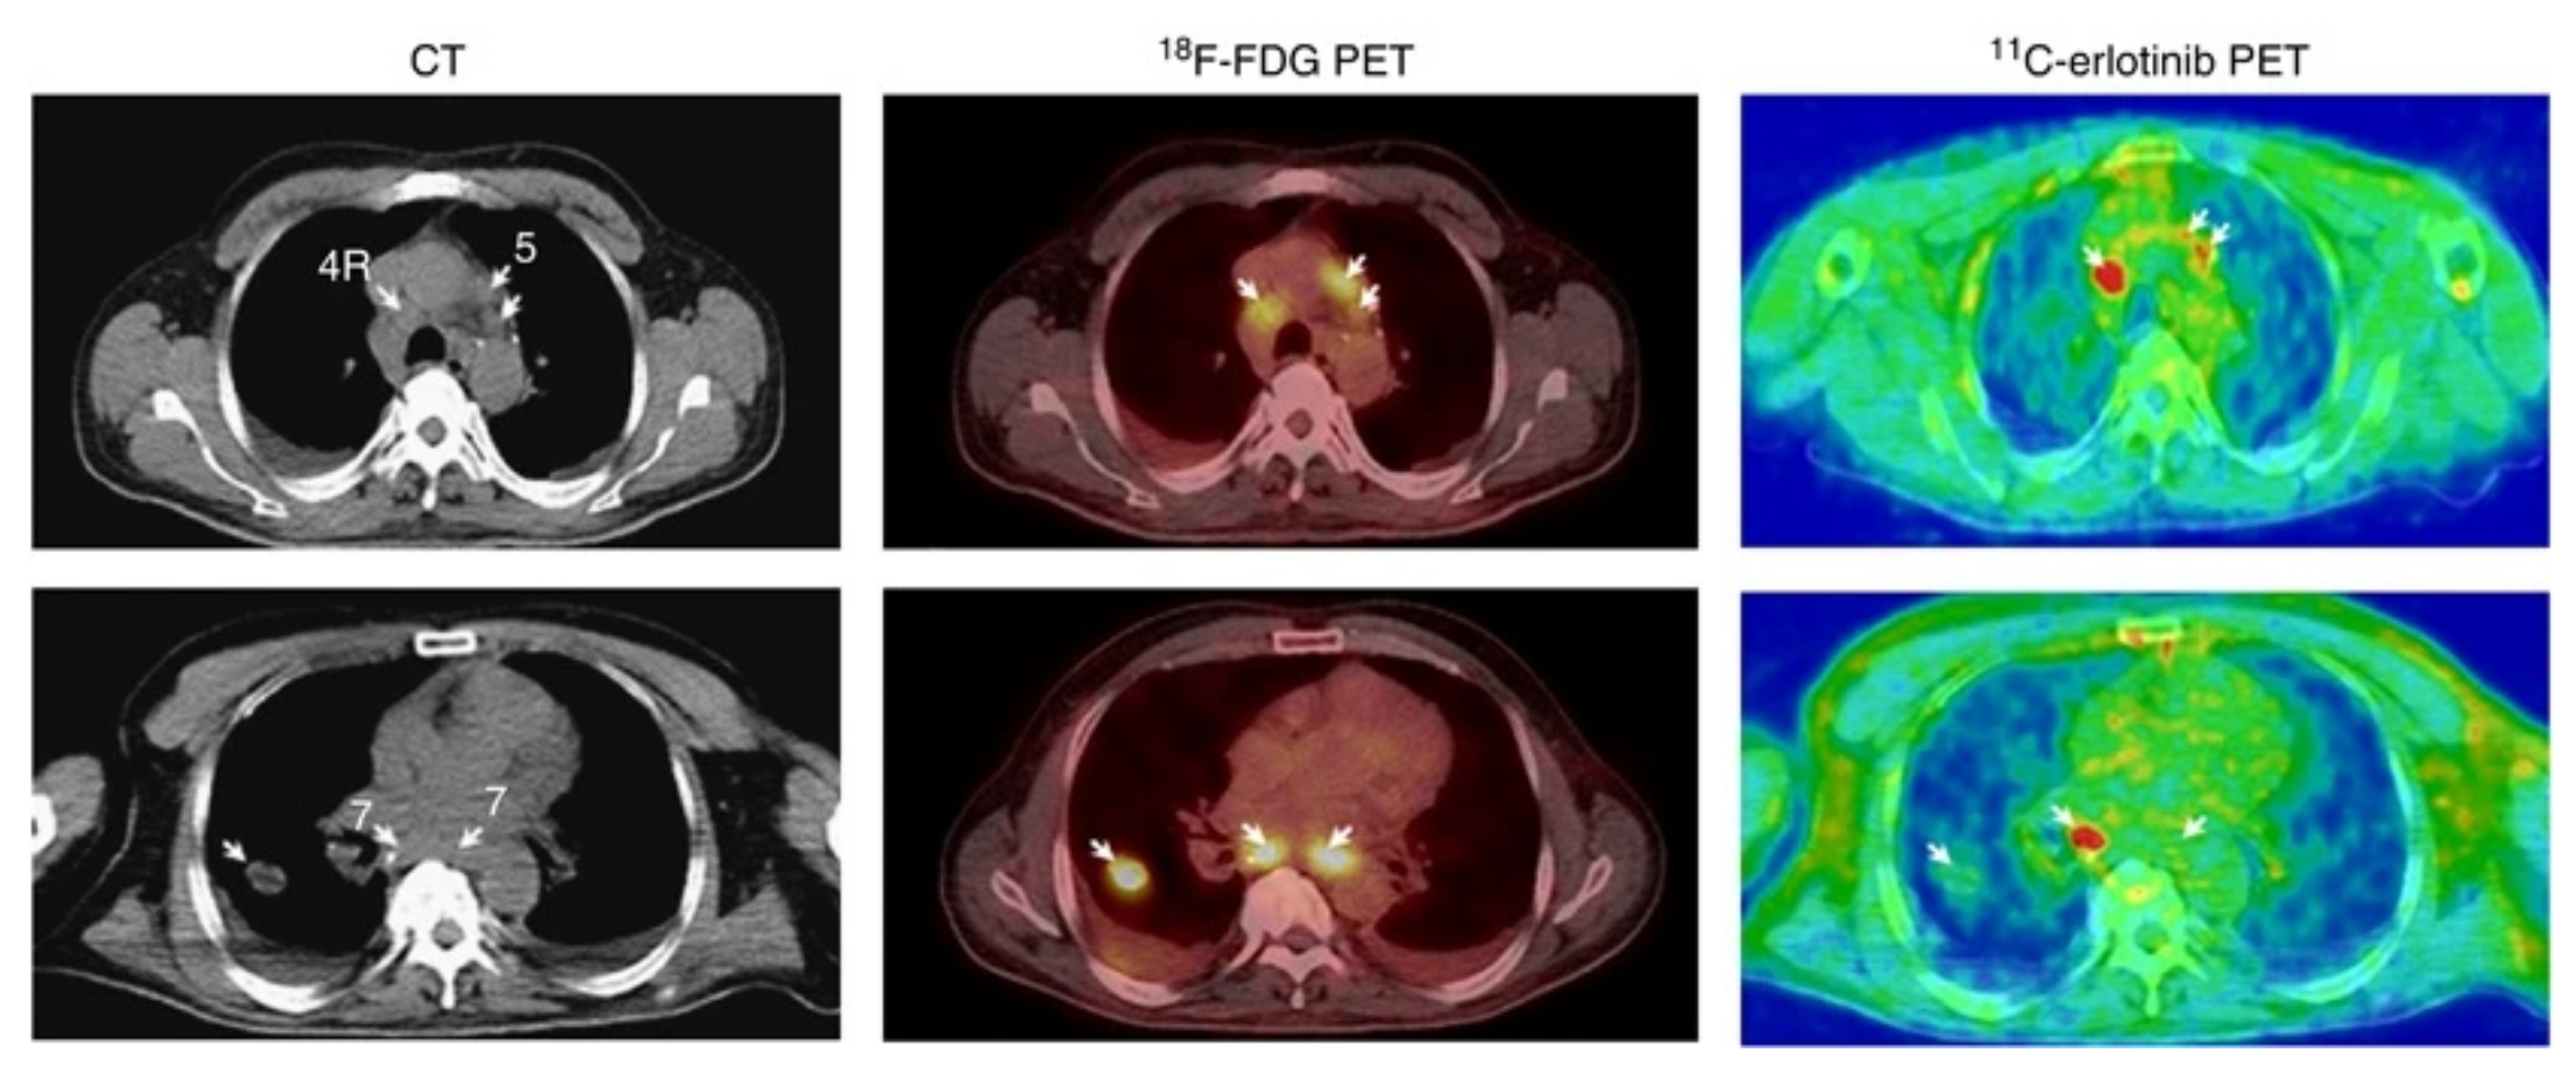

The ability of [6-O-methyl-11C]erlotinib to identify the patients most likely to benefit from erlotinib treatment was evaluated in a clinical study where 13 patients with NSCLC received a 90 min PET/CT scan to determine the accumulation of [6-O-methyl-11C]erlotinib before the initiation of erlotinib treatment. Twelve weeks after initiation, five patients exhibited stable disease, of which three displayed [6-O-methyl-11C]erlotinib hotspots. A variation in the tracer accumulation in different tumors in the same patient was observed (Figure 13). It was suggested that not all tumors or metastases would express the same driving mutations or statuses. Unfortunately, the EGFR mutational status was not confirmed in the study to further investigate this option [103]. The same authors were also involved a case study where the uptake of [6-O-methyl-11C]erlotinib corresponded to metastatic lesions in the brain of a NSCLC patient with an EGFR Del19 mutated lung tumor [104].

Figure 13.

The observed variation in [6-O-methyl-11C]erlotinib accumulation in different NSCLC tumor foci in the same patient. Adapted from [103], with permission from Springer Nature.

Bahce et al., quantified the tumor uptake and correlated uptake to the EGFR mutational status of the tumors. Ten patients with NSCLC were enrolled in a study, five lacking and five expressing an activating EGFR Del19 mutation. The volume of distribution of [7-O-methyl-11C]erlotinib was significantly larger in all subjects in the group with Del19 mutation-positive tumors compared to the group with wild-type EGFR or exon 20 mutations. Three of the five patients with Del19 mutated tumors had a partial response to erlotinib treatment. As some of the patients in the study had received TKIs prior to the study, resistance mutations might have been present at the time of the study. This could in turn have also impacted the tracer uptake [89].

In the follow-up clinical study, the capability of the tracer to image tumors expressing EGFR activating mutations in patients on or off erlotinib treatment was evaluated. A decrease in tumor uptake was observed during erlotinib treatment. Similar to preclinical observations [87], it was observed that the intact tracer fraction in arterial plasma samples and the arterial blood activity was higher in patients on erlotinib treatment. It was established that T/B ratios at 40–60 min correlated well with VT values, while SUVs did not [105].